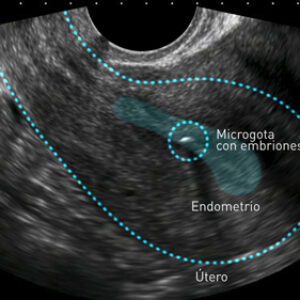

Gracias a este novedoso instrumento, es más efectivo transferir un solo embrión, lo que puede reducir los partos gemelares o múltiples